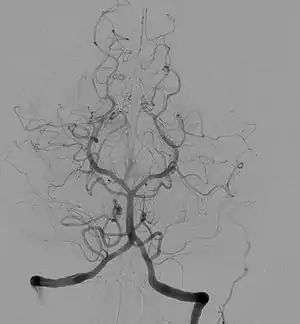

![]() Angiogram showing a transverse projection of the vertebrobasilar and posterior cerebral circulation. | |

آنژیوگرافی مغزی یک آزمایش تشخیصی است که در آن از اشعه ایکس استفاده میکنند. آنژیوگرافی مغزی میتواند به پزشک کمک کند تا به بررسی انسداد یا سایر اختلالات در رگهای خونی سر و گردن بیمار بپردازد.

انسداد یا ناهنجاری در مغز میتواند منجر به سکته مغزی یا خونریزی در مغز شود. برای انجام این آزمایش، یک لوله پلاستیکی از راه برشی در بازو یا ران به شریان رفته و پس از رسیدن به محل مورد نظر ماده کنتراست ید در آنجا تزریق میشود.

مواد کنتراست به اشعه ایکس کمک میکند تا تصاویری واضح از رگهای خونی مغز ایجاد کند تا پزشک بتواند هر گونه انسداد یا ناهنجاری را شناسایی کند.[3]